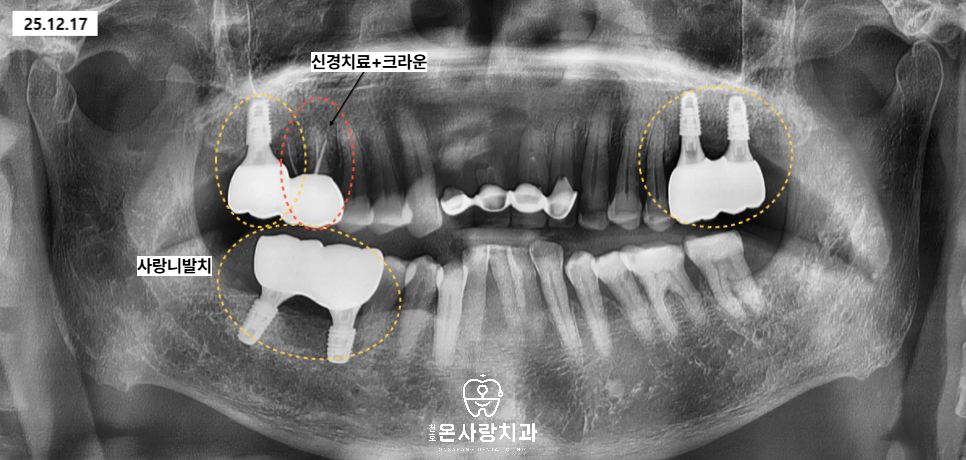

천호동치과에 처음 내원하셨을 때

왼쪽 위와 오른쪽 위아래의 어금니는

이미 상실되어 치아가 없는 상태였습니다.

그 중 오른쪽 위의 큰어금니는

정밀 검사 결과 뿌리와

주변 치조골 상태가 비교적 양호하여,

신경치료 후 엔도 및 크라운을 통해

치아를 살리는 방향으로 계획하였습니다.

기능과 수명을 모두 고려했을 때

자연치아를 유지하는 것이

환자분께 가장 유리하다고

판단했기 때문입니다.

반면 이미 치아가 상실되어

기능을 하지 못하는 부위는

임플란트를 통해 씹는 기능을

회복하는 치료를 진행하였습니다.